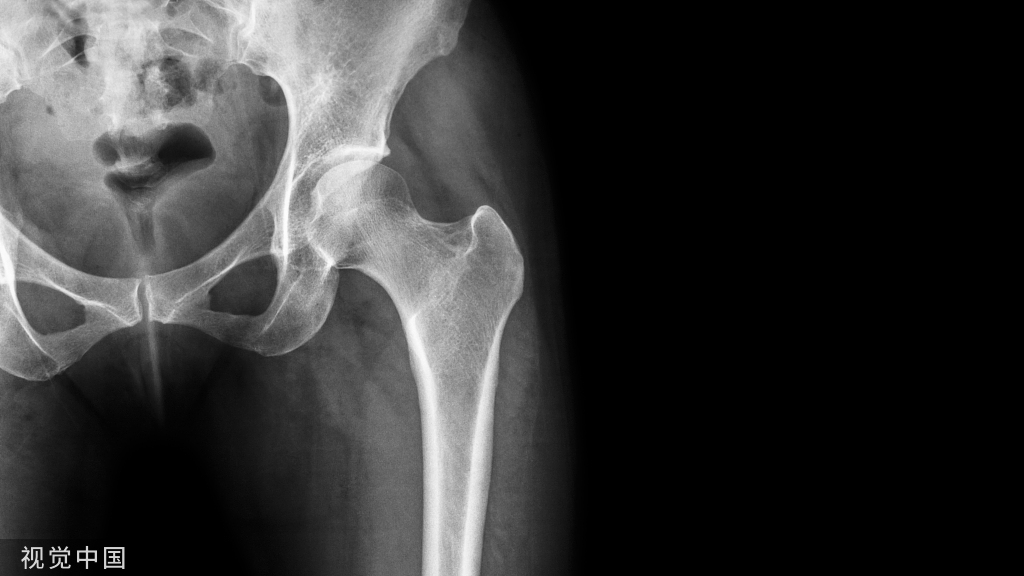

02、首个骨盆复位机器人,精度可达毫米级

骨盆骨折复位问题是世界性难题,手术操作难度极高,是典型的未被满足的临床需求。美、日、德等发达国家均围绕“骨盆骨折闭合复位”开展了大量的研发工作,但一直以来仍未有成型的系统进入临床应用。

在不断的攻坚克难过程中,罗森博特终于解决了这一世界性难题,研发成功国际首创的智能化骨折复位机器人,可有效弥补现有的骨科手术机器人复位功能缺失,同时有效提高骨盆骨折特别是高龄脆性骨折闭合复位手术成功率。目前国际上都没有一款可以用于骨折复位的手术机器人产品,罗森博特做的是真正意义上的国际原始创新,没有借鉴和参考,能凭借的是近20年医工交叉协同创新形成的积累和默契。

国际上专家认为,骨盆骨折通过复位使骨折端的移位能够达到10毫米以内即为优良,而智能化骨折复位机器人的复位操作,平均三维精度达到3.41毫米,明显优于徒手复位的精度。